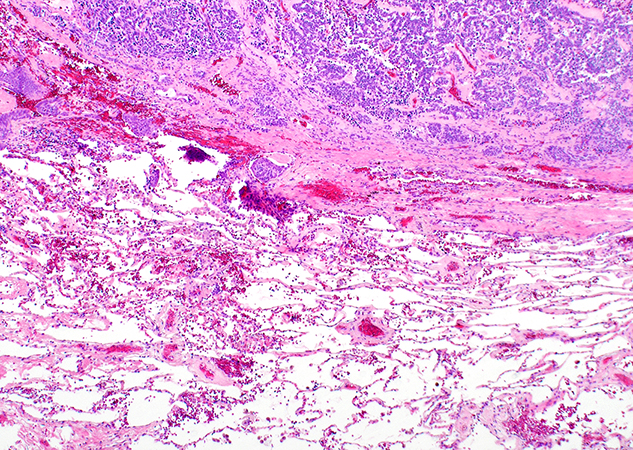

Clinical History: A 73-year-old woman with prior history of invasive ductal breast carcinoma status-post surgical resection, radiation, and endocrine therapy presented to her physician with lingering cough after COVID-19 infection. A CT scan detected a 1.8 cm indeterminate nodule in the left upper lobe with relatively smooth margins. PET/CT scan showed that the nodule was hypermetabolic with FDG avidity similar to that of the liver, suspicious for metastatic disease. The patient underwent a core biopsy of the nodule (not shown) and later left upper lobectomy. Histologic sections of the nodule are shown in Figures 1 through 6. A Fontana-Masson stain is shown in Figure 5.

The presence of uncommon morphologic features in neuroendocrine tumors can create diagnostic confusion. Evaluation of a cellular spindle cell neoplasm with scattered pigment in the lung may be confused with spindle cell melanoma (either primary or metastatic). The lack of a prior history of melanoma does not favor metastatic disease, and the bland cytologic features would be uncommon in melanoma. Pulmonary spindle cell neuroendocrine tumors should also be distinguished from pulmonary thymoma, spindle cell carcinomas, solitary fibrous tumor, and synovial sarcoma. Immunohistochemistry is helpful to establish the diagnosis of a neuroendocrine tumor, positive for CD56, synaptophysin, chromogranin and INSM1 in most cases. In the current case, neuroendocrine differentiation was confirmed in the core biopsy (not shown). Melanocytic markers (S100, HMB-45, MART-1, SOX10) are expressed only in cells containing melanin, but they are negative in the non-pigmented neoplastic neuroendocrine cells. Neuroendocrine tumors are negative for CD34, STAT6 (positive in solitary fibrous tumor), TLE1 (positive in synovial sarcoma) and p40 (positive in thymoma). Spindle cell carcinomas have significant atypia, are positive for keratins, but are negative for neuroendocrine markers. None of these tumors contain melanin.

Pigmented neuroendocrine tumors are not exclusive of the lung, with some descriptions in the thymus and the gastrointestinal tract. It is hypothesized that along with hormone production, melanin may be produced by neuroendocrine cells due to a divergent differentiation.

Most pigmented neuroendocrine tumors reported have been typical carcinoids, and only rarely atypical carcinoids. The identification of melanin in a pulmonary neuroendocrine tumor does not confer any prognosis. A pigmented neuroendocrine tumor should be graded using conventional diagnostic criteria, as done in the current case.

Take home message for trainees: Rarely, carcinoid tumors can contain melanin creating diagnostic confusion. The most important diagnosis of exclusion is spindle cell melanoma (primary or metastatic to lung). Clinical history, morphology, special stains, and immunohistochemical stains are useful to confirm the diagnosis. Identification of melanin does not confer any prognosis to a lung neuroendocrine tumor, which should be graded according to conventional WHO criteria.